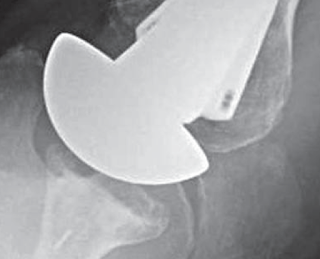

Signs of subscapularis failure in include excessive passive external rotation

and weakness of the belly press

and sometimes anterior instability.